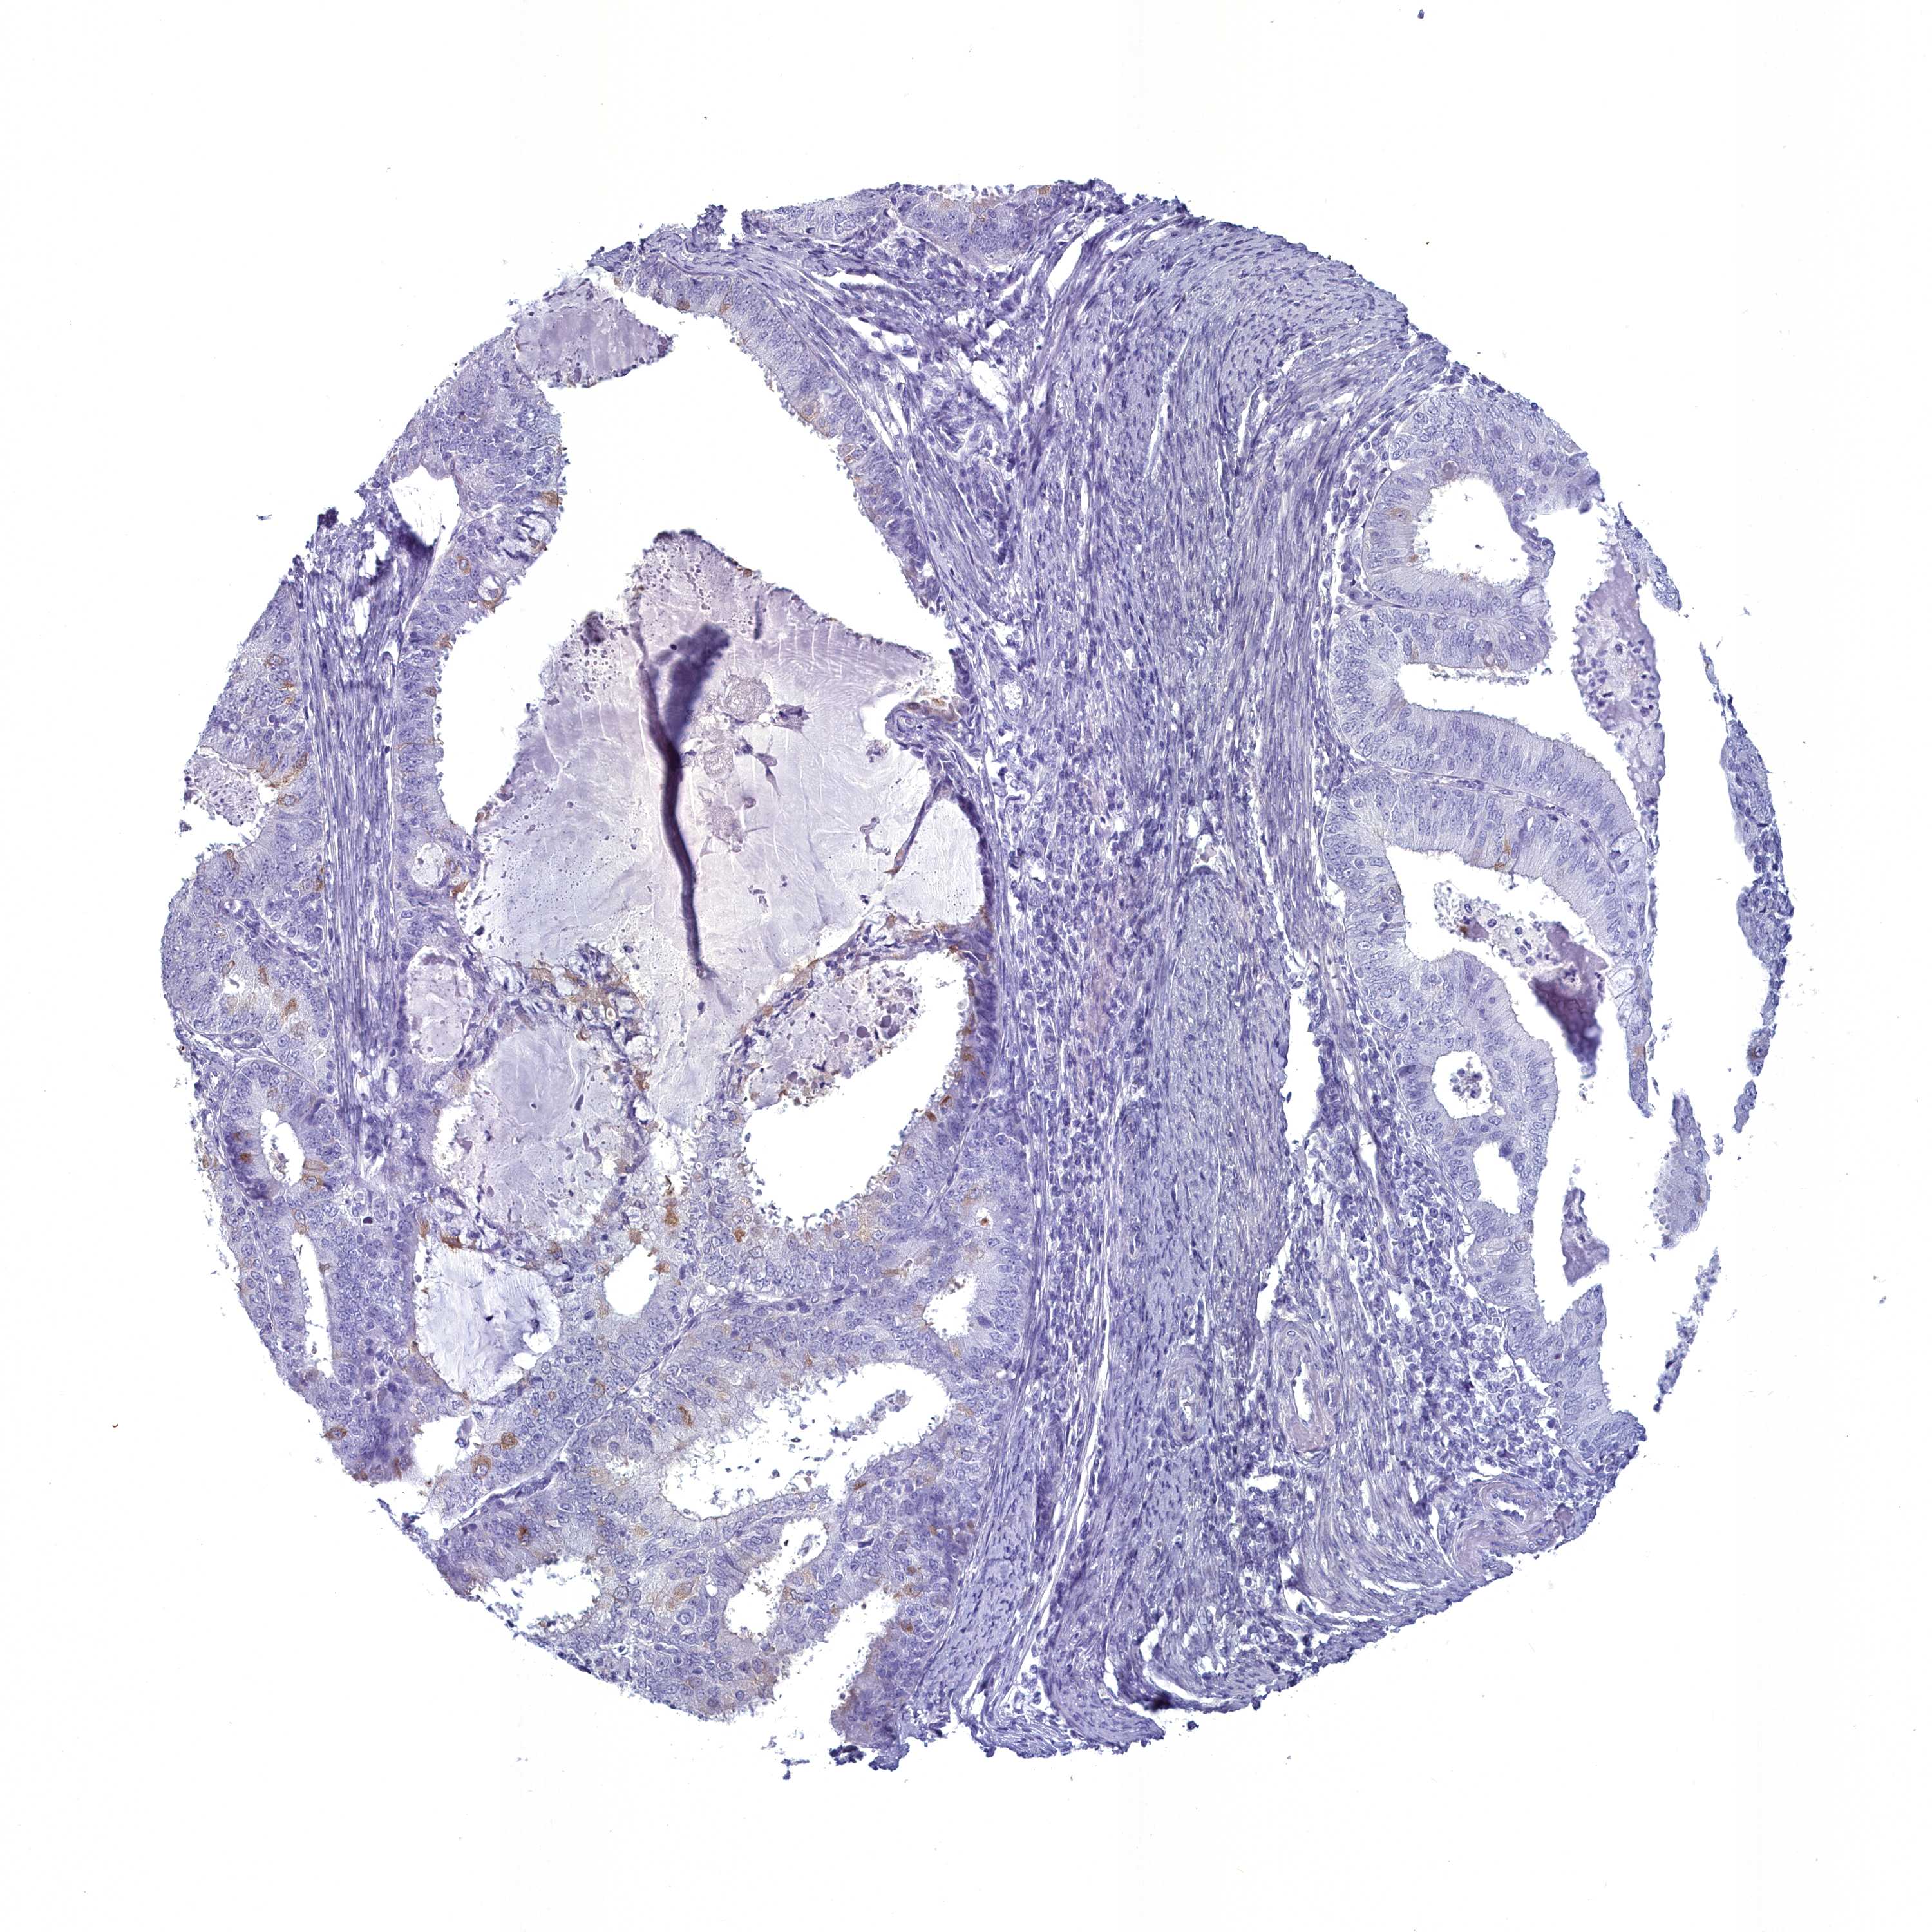

ENDOMETRIAL CANCER - Protein expressioni

A mouse-over function shows sample information and annotation data. Click on an image to view it in a full screen mode. Samples can be filtered based on level of antibody staining by selecting one or several of the following categories: high, medium, low and not detected. The assay and annotation is described here.

Note that samples used for immunohistochemistry by the Human Protein Atlas do not correspond to samples in the TCGA dataset.

Antibody stainingi

Antibody staining in the annotated cell types in the current human tissue is reported as not detected, low, medium, or high, based on conventional immunohistochemistry profiling in selected tissues. This score is based on the combination of the staining intensity and fraction of stained cells.

Each image is clickable and will lead to virtual microscopy that enables deeper exploration of all samples and also displays staining intensity scores, fraction scores and subcellular localization as well as patient and tissue information for each sample.

Antibody HPA039061

Antibody HPA039062

Antibody CAB015442

Antibody CAB022600

Staining

High

Medium

Low

Not detected

Intensity

Strong

Moderate

Weak

Negative

Quantity

>75%

75%-25%

<25%

None

Location

Nuclear

Cytoplasmic/membranous

Cytoplasmic/membranous,nuclear

Adenocarcinoma, NOS